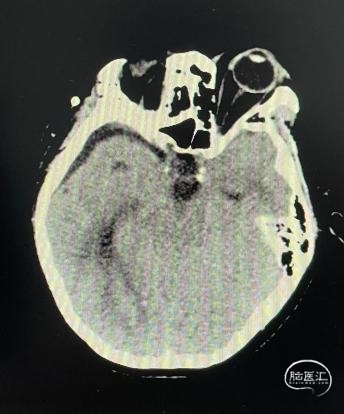

头部CT平扫显示:全鞍型蝶窦,鞍区-鞍上区-第三脑室可见一混杂密度肿块,内可见多发钙化灶,最大层面大小约43mm*35mm(左右径-前后径),CT值30HU,双侧脑室明显扩张,室旁可见对称性条片状低密度灶。